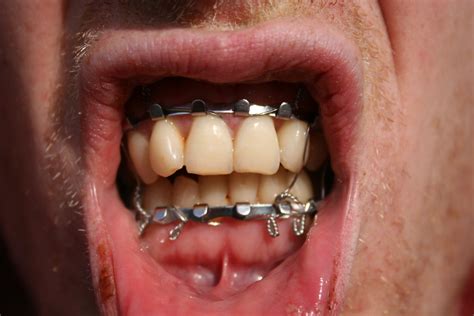

Disadvantages Of Jaw Wiring Maxillofacial Hardware Surgery T